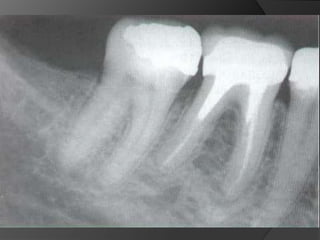

Diagnóstico y Planificación MultidisciplinariaEl examen clínico y la historia clínica nos darán información sobre los factores locales y sistémicos que pueden tener gran influencia en la obtención de un pronóstico para el tratamiento propuesto

Diagnóstico y Planificación MultidisciplinariaHistoria ClínicaAnamnesisFotografía clínica Montaje modelos de estudioEncerados DiagnósticosEvaluación Radiográfica Radiografías PeriapicalesRadiografía PanorámicaEvaluación DentalEvaluación PeriodontalEvaluación EndodónticaEvaluación OclusalEvaluación Articular?